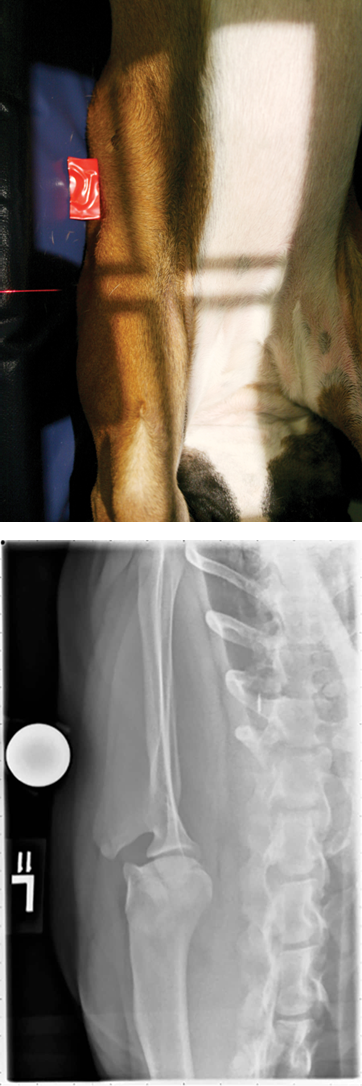

Describe the position of dog in caudo-cranial view for shoulder radiograph

The dog is put in dorsal recumbency with the limb to be radiographed pulled into extension (X-rays enter caudal aspect and exits cranial aspect of the shoulder)

The limb is pulled slightly away from the midline (approx. 5 degrees)

A sandbag may be use to push the head and neck slightly away from the limb to reduce superimposition

Use L/R label